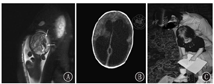

在新生儿期的MRI中,出血病变可能非常显著,但也可能表现仅有某种程度的脑萎缩。婴儿自发性出血病因复杂,这可能决定预后。围生期白质损害与认知缺陷有关;损害越严重,认知的缺陷也就越严重。如果皮质脊髓束和/或基底神经节和丘脑有额外的累及,就可能发生运动障碍。特别注意的是,部分严重早期出血患儿,有较好预后(图9)[10]。

图9

1例宫内严重脑出血患儿的预后 A:孕29周胎儿T2:左侧额叶出血伴脑室扩张,出血周围存在水肿(TR/TE=3 630/90 ms);B:出生后1 d:侧脑室和第三脑室严重扩张,与大脑导水管水平的严重梗阻性脑积水相一致,大脑实质变薄,左侧较右侧显著(第2天进行了手术);C:2岁时,患儿坐在母亲腿上欣赏收到的生日贺卡

Prognosis of a child with severe intracerebral hemorrhage A:fetal magnetic resonance imaging T2-weighted half-fourier acquisition single-shot turbo spin-echo sequence at 29 weeks of gestational age.Arrows indicate left frontal hemorrhage with ventricular extension.The hemorrhage is surrounded by edema (TR/TE=3 630/90 ms);B:computed tomography of the head at 1 day of age,demonstrating severe dilatation of the lateral and third ventricles,consistent with severe obstructive hydrocephalus at the level of the cerebral aqueduct,and thinning of the brain parenchyma,left more than right.She underwent surgery the next day;C:patient at age 2 years,sitting in her mother′s lap,admiring a card she received for her second birthday